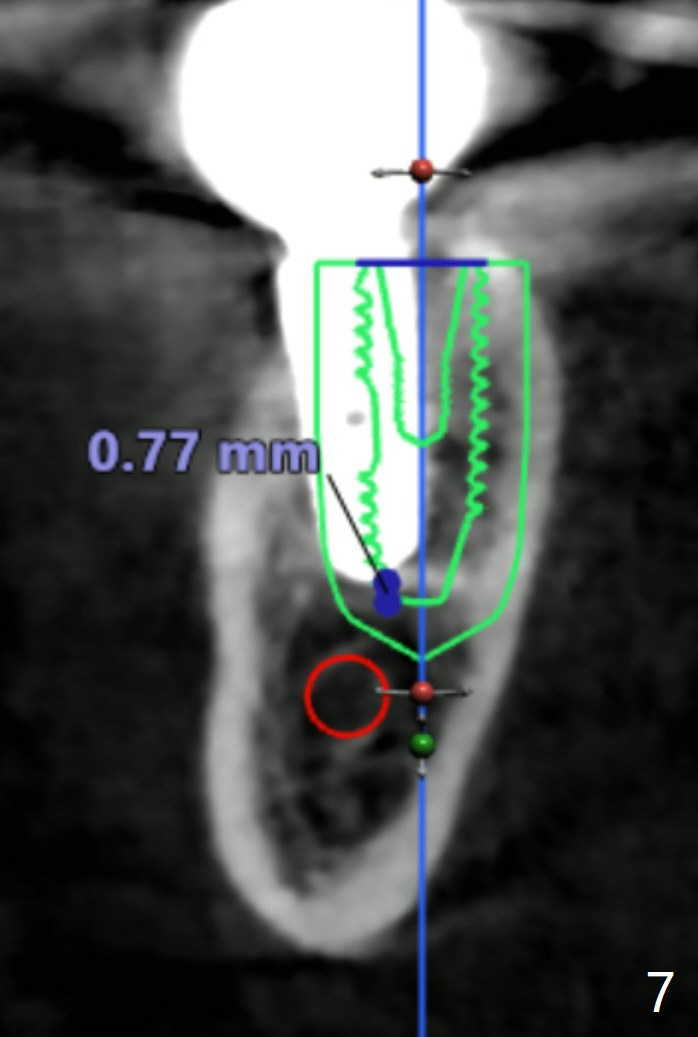

Twenty six months post cementation, periimplantitis develops buccally at #30 (Fig.1) due to buccal (B) placement (Fig.2) with buccal thread exposure (red line), as compared to the same sized implant at #19 (Fig.3). After removal of the crown and abutment and incision, use Titanium brush to clean the exposed threads. Following implant removal and removal of the lingual bone, place the same implant lingually (Fig.4 arrow) with the used-to-be-exposed surface facing lingual (Fig.4 red line). The buccal gap will be filled with autogenous bone harvested lingually and allograft. Use 2-3 pieces of PRF membranes to close the wound, i.e., to bury the implant. A 5x13 mm implant (Fig.5) placed lingually (Fig.6 L) appears to be unable to gain more than .77 mm native bone (Fig.7). Lab declines to make a guide.